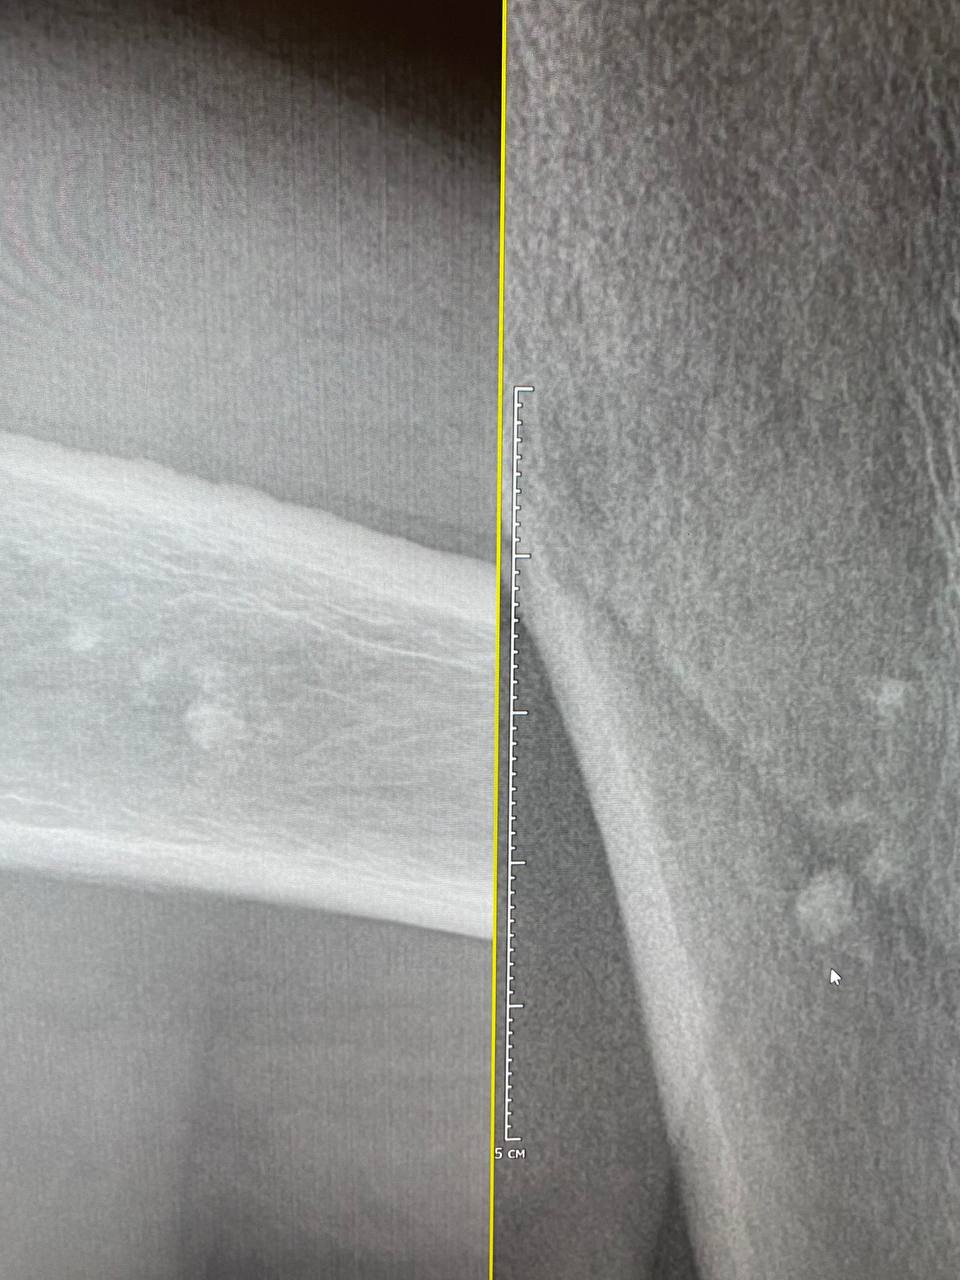

Здравствуйте, подскажите пожалуйста похожи ли эти изменив в верхней трети плечевой кости на энхондрому

Да может